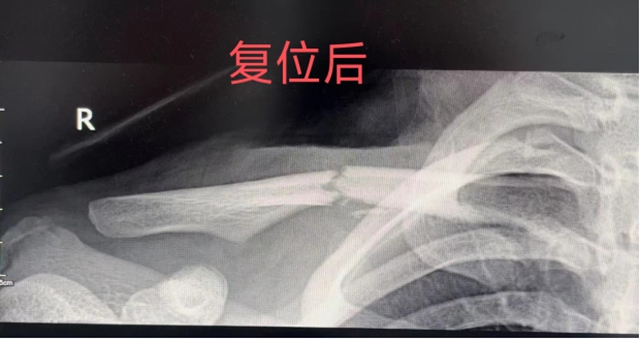

经过X光检查,小宇被确诊为锁骨骨折,且骨折移位较大。医生建议进行手术治疗,但这个消息让小宇的父母犯了难:孩子还小,正处于升学的关键时期,手术不仅会留下难看的手术瘢痕,而且二期还需要再次手术取出钢板,这对孩子的身体和心理都会造成一定的影响。

骨伤科创伤·正骨组的王念武医生接诊后,仔细查看了小宇的病情和之前的检查资料,一边耐心地听着父母讲述孩子的受伤经过和他们的担忧,一边在心里思索着治疗方案。虽然小宇的骨折移位严重,但受伤时间短,而且孩子和家属都愿意积极配合治疗,这让王医生觉得还有复位的可能。他将自己的想法向上级医师请示后,得到了支持,决定当天就为小宇进行中医手法复位。

治疗室内,王念武医生让小宇放松身体,随后便和几位医护人员默契配合开始了复位。擒拿、牵引、端提、环绕、升降…… 一系列专业而娴熟的手法在小宇的肩部施展。小宇虽然疼得直冒汗,但还是咬着牙,按照医生的指导努力配合着。时间一分一秒地过去,经过几次调整,终于,骨折部位成功复位了!大家都松了一口气,脸上露出了欣慰的笑容。随后,医生们为小宇用上了特制的杉树皮小夹板进行固定,并外敷了特色院内中药制剂。

据王念武介绍,锁骨位于皮下,俗称美人骨,位置表浅,受外力作用时易发生骨折,发生率占全身骨折的5%~10%。由于暴力导致骨折移位及肌肉牵拉,骨折后断端往往移位较大,经过手法整复及固定后绝大数可以保守治疗。